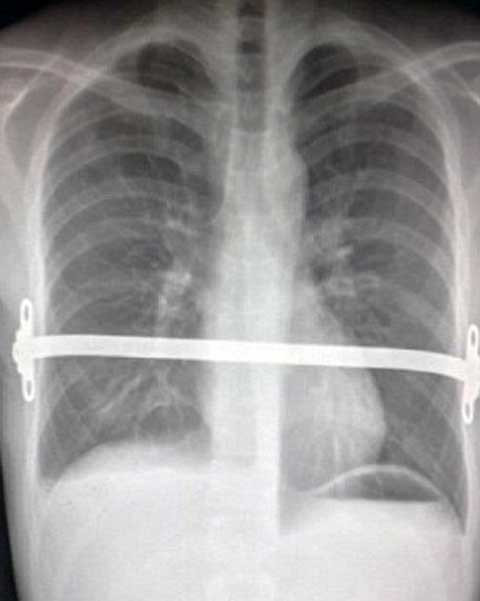

| Các bác sĩ đã sáng tạo một thanh đỡ bằng kim loại gắn cố định vào ương của Dale để bảo vệ tim và phổi của anh |

Thật may mắn, các bác sĩ đã sáng tạo ra một thanh đỡ gắn cố định vào xương của Dale để bảo vệ tim và phổi giúp anh duy trì sự sống.

Hiện tại, sau 3 năm thanh đỡ bằng kim loại được gắn cố định vào xương của Dale để giúp anh bảo vệ tim và phổi đã có thể cố định được lồng ngực anh phát triển theo hướng bình thường nên các bác sĩ đã có thể tháo bỏ thanh đỡ này ra.